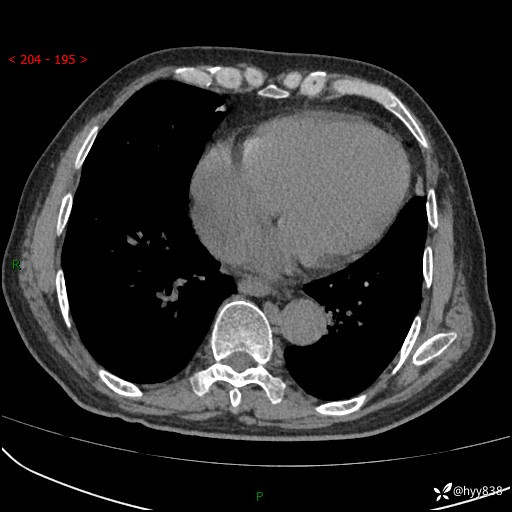

主诉:检查发现心脏肿物1周余。

现病史:患者一周余前因腹胀就诊我院消化科门诊,查心脏彩超提示右房内异常回声(粘液瘤?),无明显心慌、气喘、胸闷,无明显胸痛、咳嗽咳痰等不适,活动量增加后出现心慌、气喘不适。现为求进一步治疗,就诊我科,门诊遂以“心脏肿物”收入院。 自发病以来,精神睡眠一般,食欲尚可,大小便正常,体力下降,体重无明显变化。

胸部CT平扫+增强